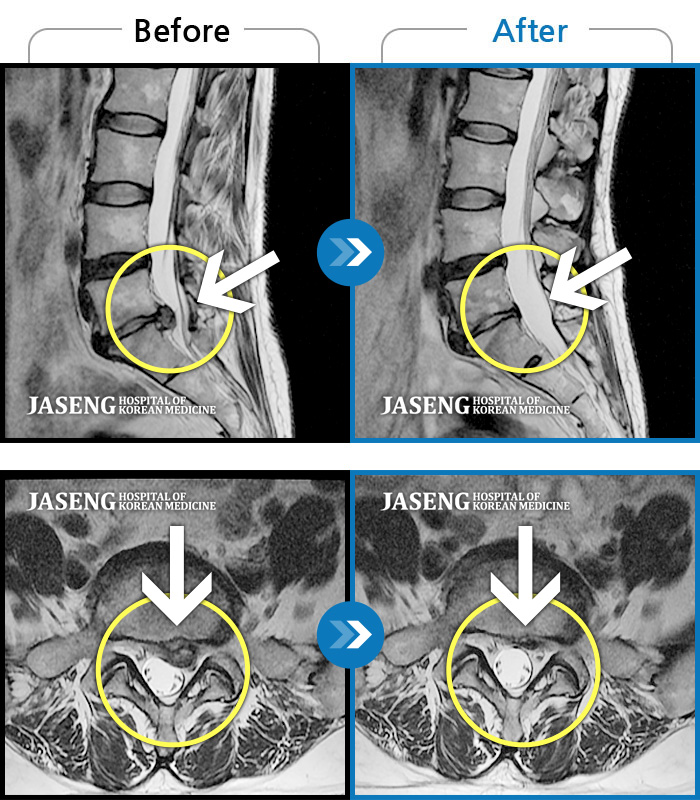

Before

After

환자에게 사전 동의를 받아 동일 조건에서 촬영되었습니다.

개인에 따라 치료 후 부작용이 발생할 수 있으니 의료진과 상담 후 치료를 진행하시기 바랍니다.

왼쪽 허리 통증 및 왼쪽 하지의 저림, 감각이상, 족하수

요부 및 우하지 극통으로 거동이 불가